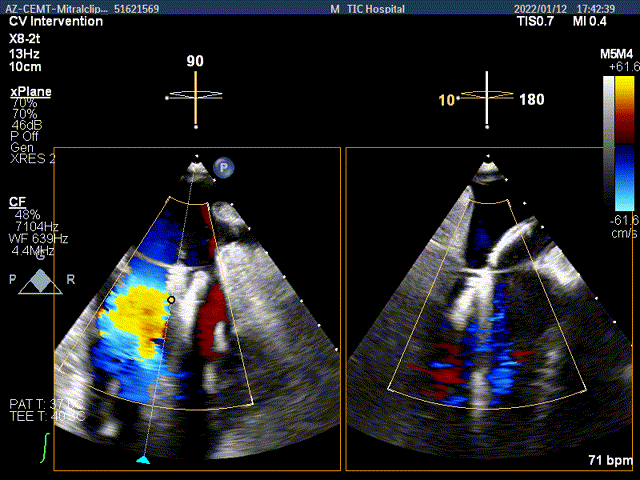

x-plane验证前后叶抓捕后bond明显

x-plane验证前后叶抓捕后跳跃征明显

3D-view验证两个夹子位置稳定,排列紧密

3D-Color-view验证微少量残余返流